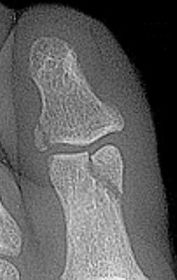

| Describe what is occurring at the head of the 3rd met | Freiberg’s infarction (avascular necrosis of the metatarsal head) |